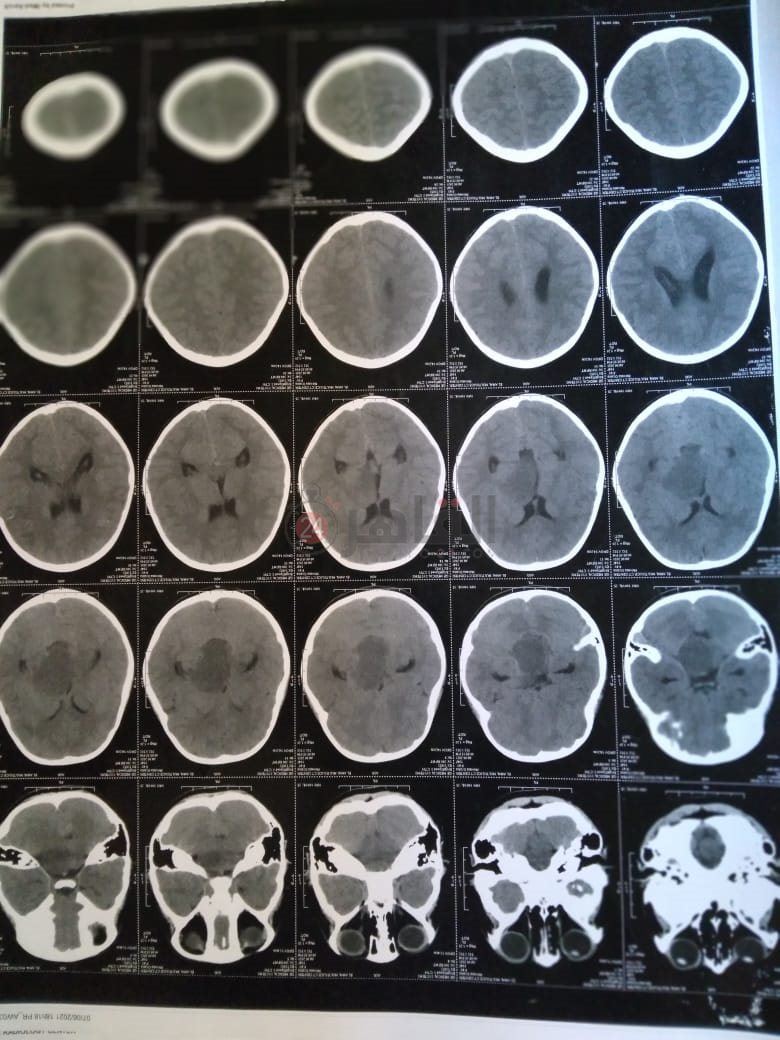

وأضاف: "أجرينا أشعة مقطعية لها لم يظهر بها أي شيء، ثم طلب الطبيب إجراء أشعة رنين على المخ، وهنا تبين وجود بؤرة سرطانية بالمخ، مشيرًا إلى أن:" الدكتور طلب مني أذهب إليه لوحدي من غير الأم والبنت، وقالي إن في ورم بس مش عارفين نوعه خبيث ولا حميد".

وأوضح أن حالة نجلته تتدهور بسرعة كبيرة، حيث أصُيبت حاليًا بشلل نصفي بالجانب الأيمن، لأن البؤرة حجمها 2.5 سم في 4.5 سم، ومرتكزة على جانبها الأيمن، مشددًا على أنها الحالة الأولى في العائلة التي تصاب بهذا المرض.